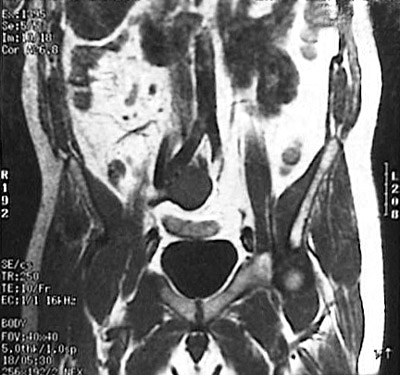

| Here is an unusual location with an unusual name, but it is part of the extra-adrenal paraganglion system and can be a site for the 10% of pheochromocytomas that are extra-adrenal. These MRI scans in coronal view above and axial view below demonstrate a pheochromocytoma of the organ of Zuckerkandl located just below and to the right of the aortic bifurcation. |